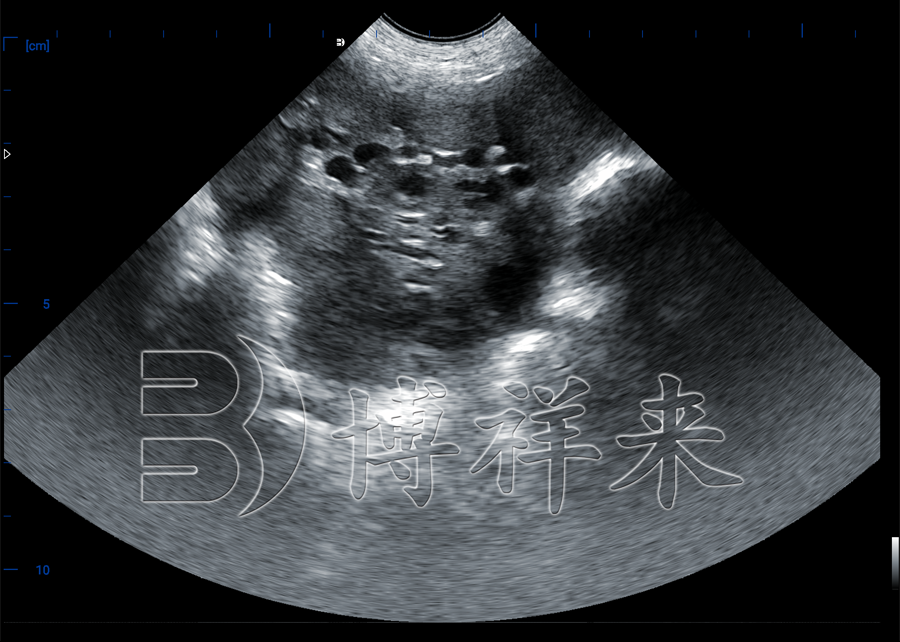

猪卵泡检测B超机:批次化管理好帮手

在现代规模化养猪场中,批次化管理已成为提高生产效率、规范繁殖流程的关键手段。而实现母猪繁殖批次统一的前提,是掌握母猪的卵泡发育状态,从而科学安排配种时间。借助猪卵泡检测B超机,养殖场可以直观判断卵巢发育情况,为母猪配种提供精准依据,是实现繁殖批次化的高效工具。

使用猪卵泡检测B超机,可快速判断卵泡是否发育成熟、是否即将排卵,从而精准调整配种时间,实现真正意义上的“配种同步,分娩集中”。

1、实时观察卵泡发育状态

可通过直肠或腹部探头清晰显示卵巢结构,检测是否有成熟卵泡,判断配种时机是否到位。